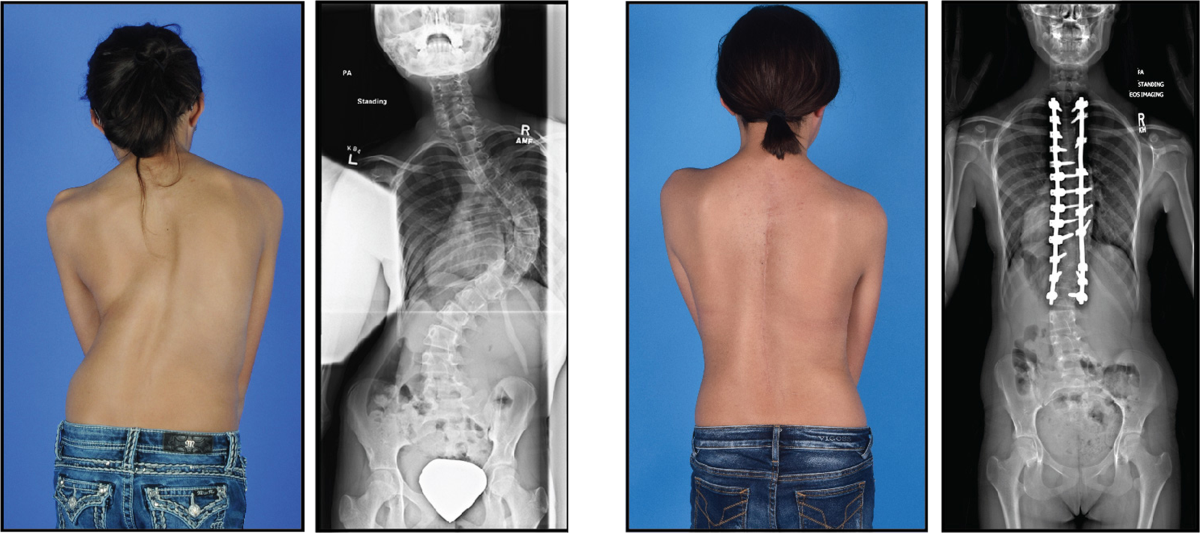

هل جراحة اعوجاج العمود الفقري للبنات تترك أثرًا واضحًا على شكل؟

في الحالات التي تحتاج تدخلًا جراحيًا (وهي نسبة قليلة)، الهدف الأساسي من الجراحة هو:

منع تطور الانحناء

تحسين التناسق العام للجسم

استعادة التوازن

كثير من الحالات الجراحية تؤدي إلى تحسن ملحوظ في الشكل مقارنة بما قبل التدخل.